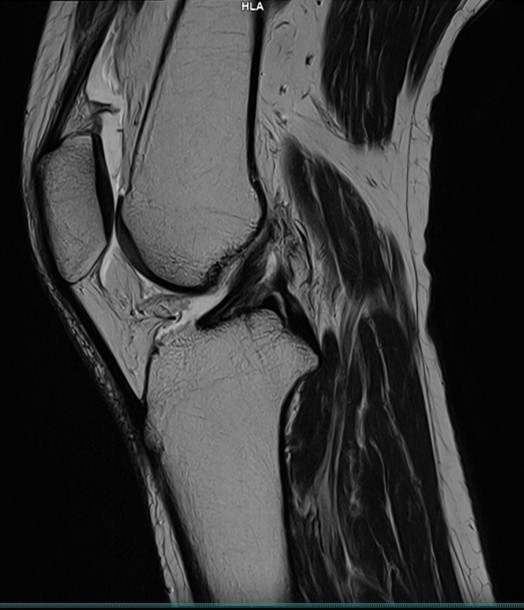

X線撮影で診断の難しい靭帯や半月板などの軟部組織を明瞭に描出することができます。また骨組織はもちろん関節や靭帯の診断に有用です。

膝関節MRI